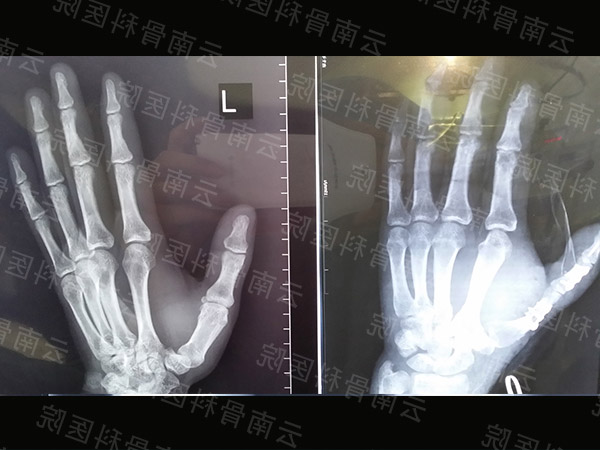

拇指Ⅰ度再造(1)

拇指Ⅰ度再造(2)

拇指Ⅱ度再造

拇指Ⅲ度再造